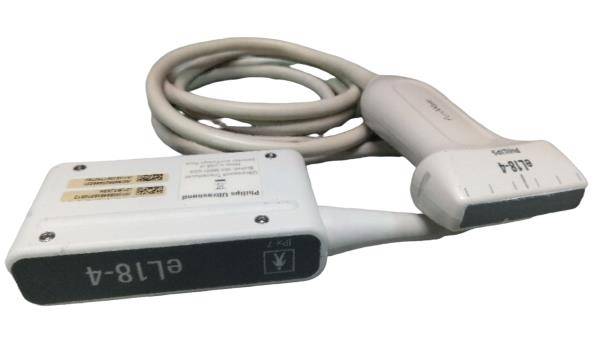

Mikrokonvexe Sonde |

1 |